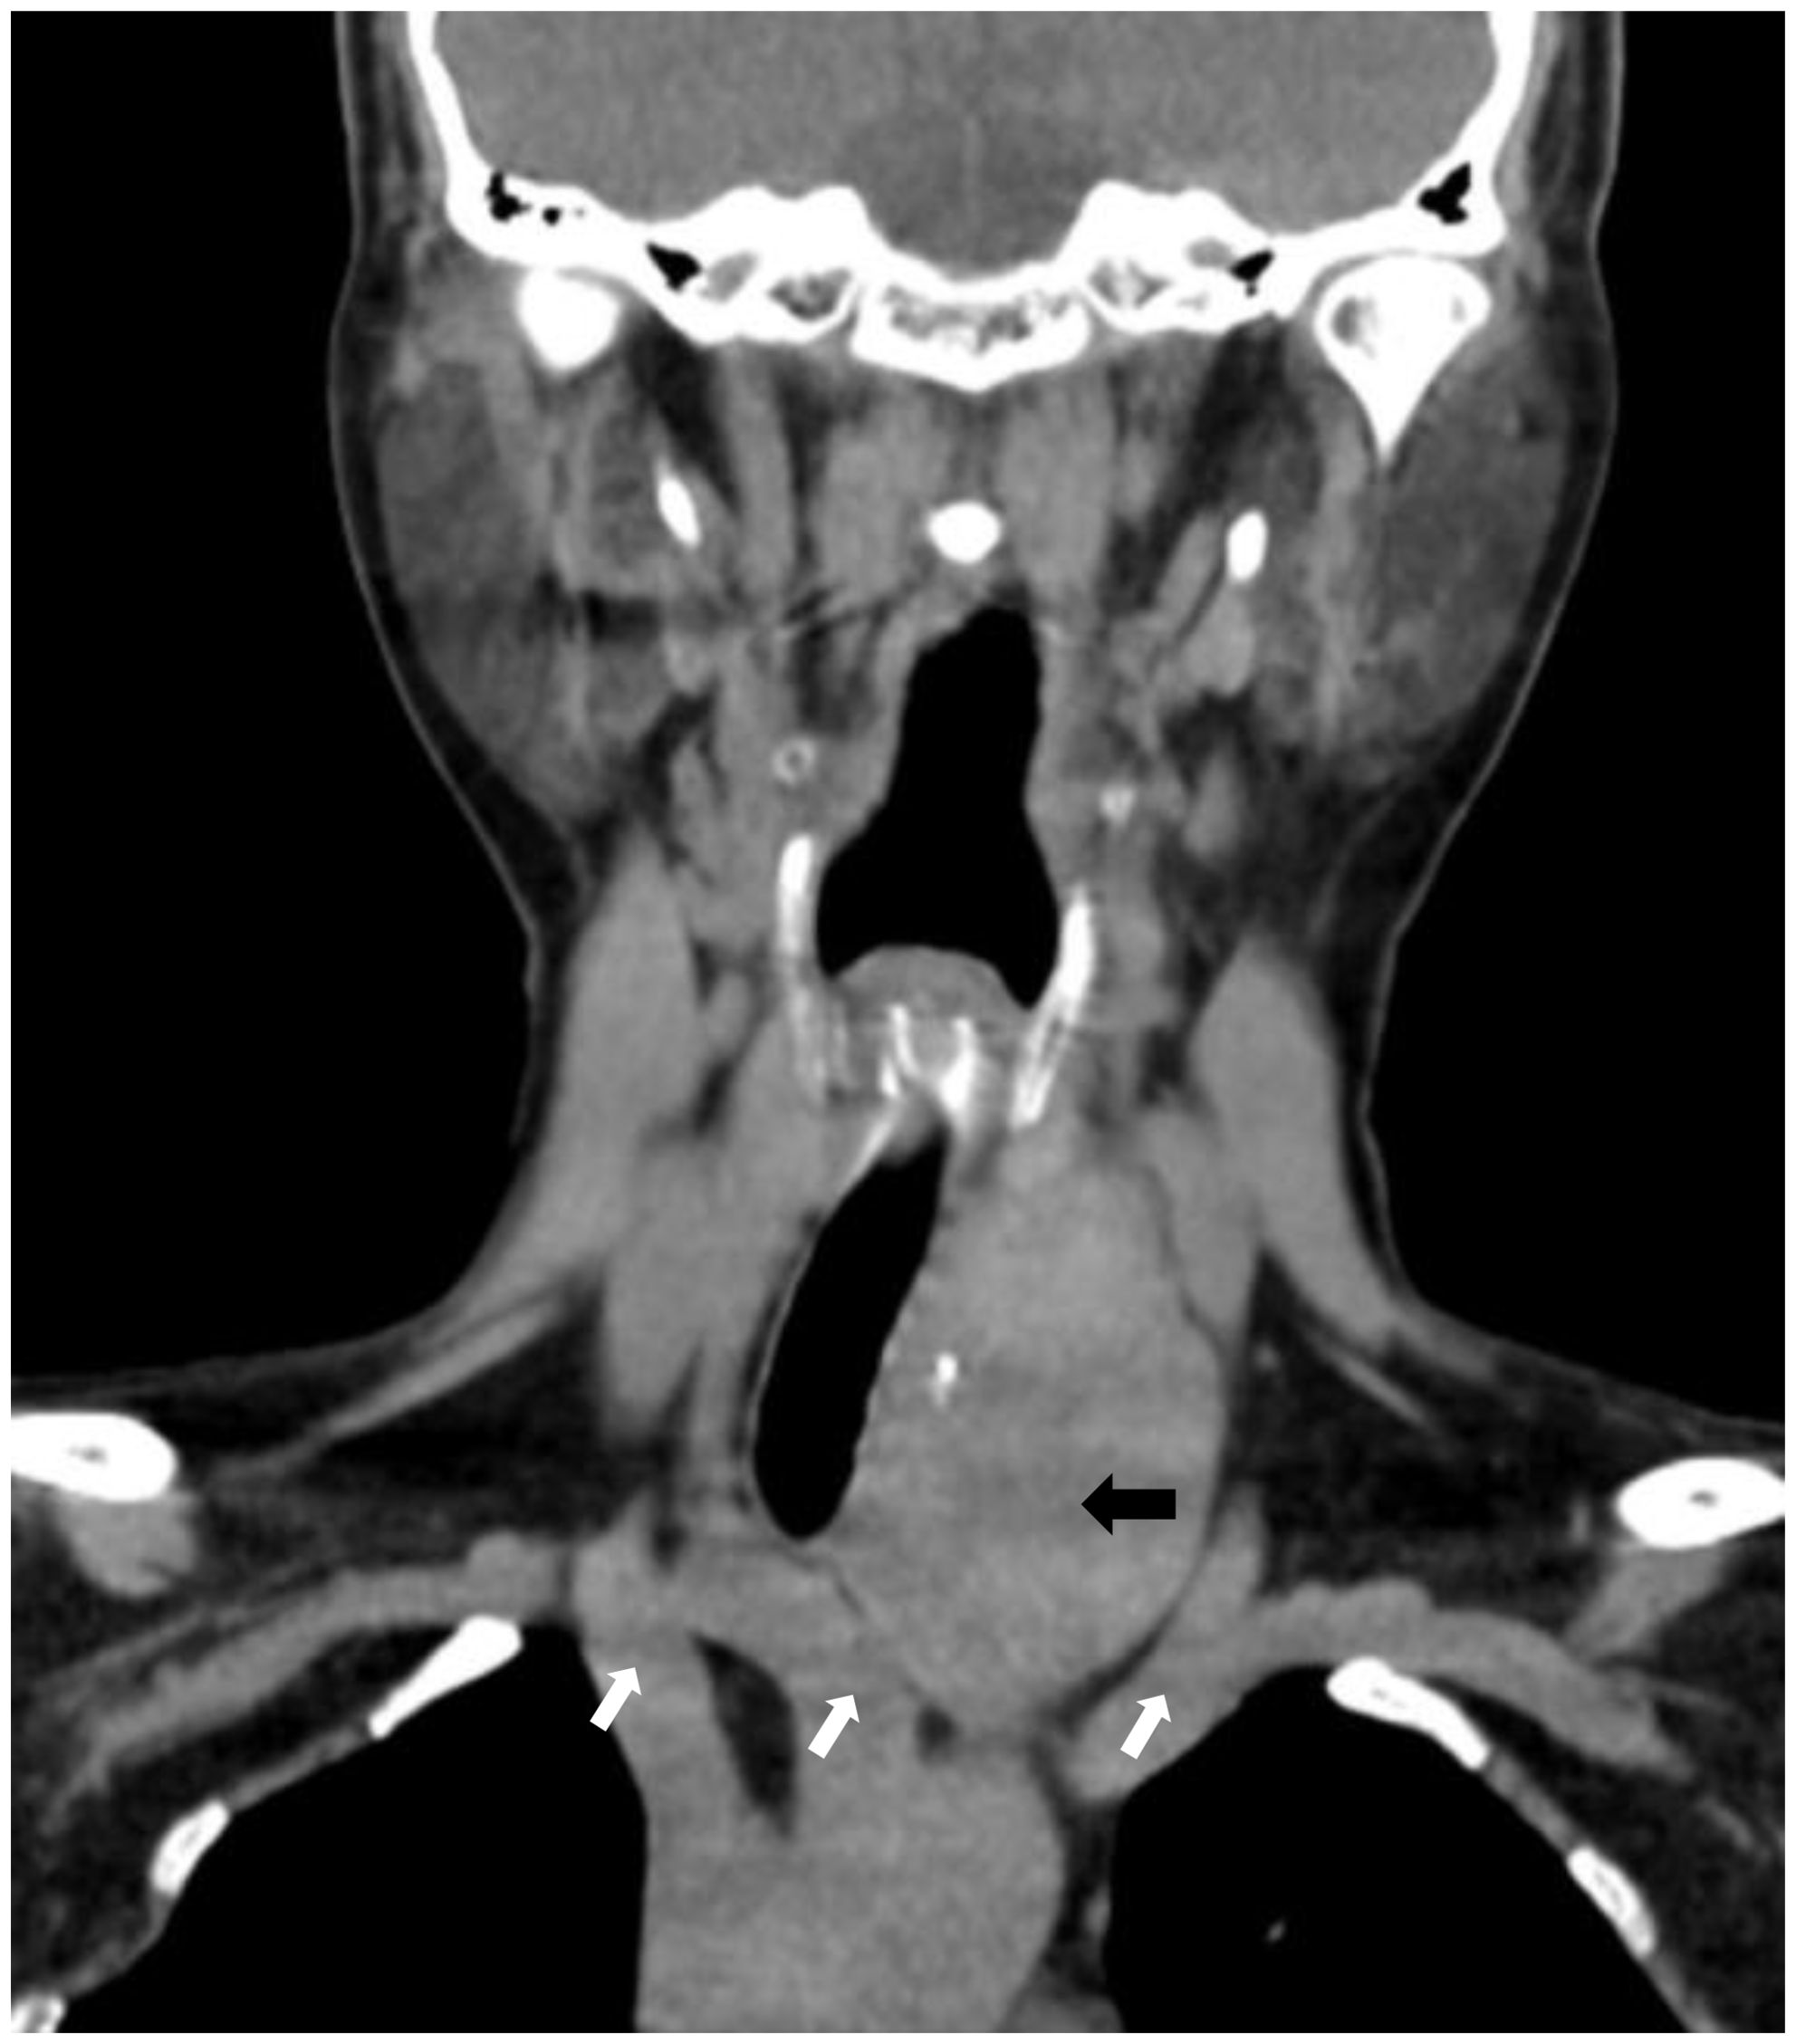

A 60-year-old female patient presented to our hospital with a history of thyroid nodules found for more than 20 years. Recently, she had developed airway compression and choking while drinking water. She had undergone a right thyroid lobectomy for benign thyroid nodules 5 years ago. After admission, CT examination showed a significant enlargement of the left thyroid lobe, with a mixed-density mass measuring approximately 4.6×4.2×4.5 cm. The lesion displaced the trachea to the right and extended into the anterior superior mediastinum, compressing the aortic arch, right subclavian artery, and left common carotid artery. Notably, the patient had a congenital vascular anomaly, with the aortic arch giving rise to the cephalic trunk, right subclavian artery, and right common carotid artery from left to right (Figure 1). The ultrasound examination showed that the left lobe of the thyroid gland was morphologically abnormal and significantly enlarged, with an inhomogeneous hypoechoic mass measuring about 4.9x4.5x4.7 cm, which was projecting into the upper mediastinum and compressing the aortic arch and its branch vessels (Figure 2). Laboratory tests for thyroid function and parathyroid function were normal, and a preliminary diagnosis of substernal goiter was made.

Figure 1. CT shows an enormous substernal goiter compressing the trachea. (black arrow). Right common carotid artery, right subclavian artery, left cephalic trunk. (image from left to right, white arrows).